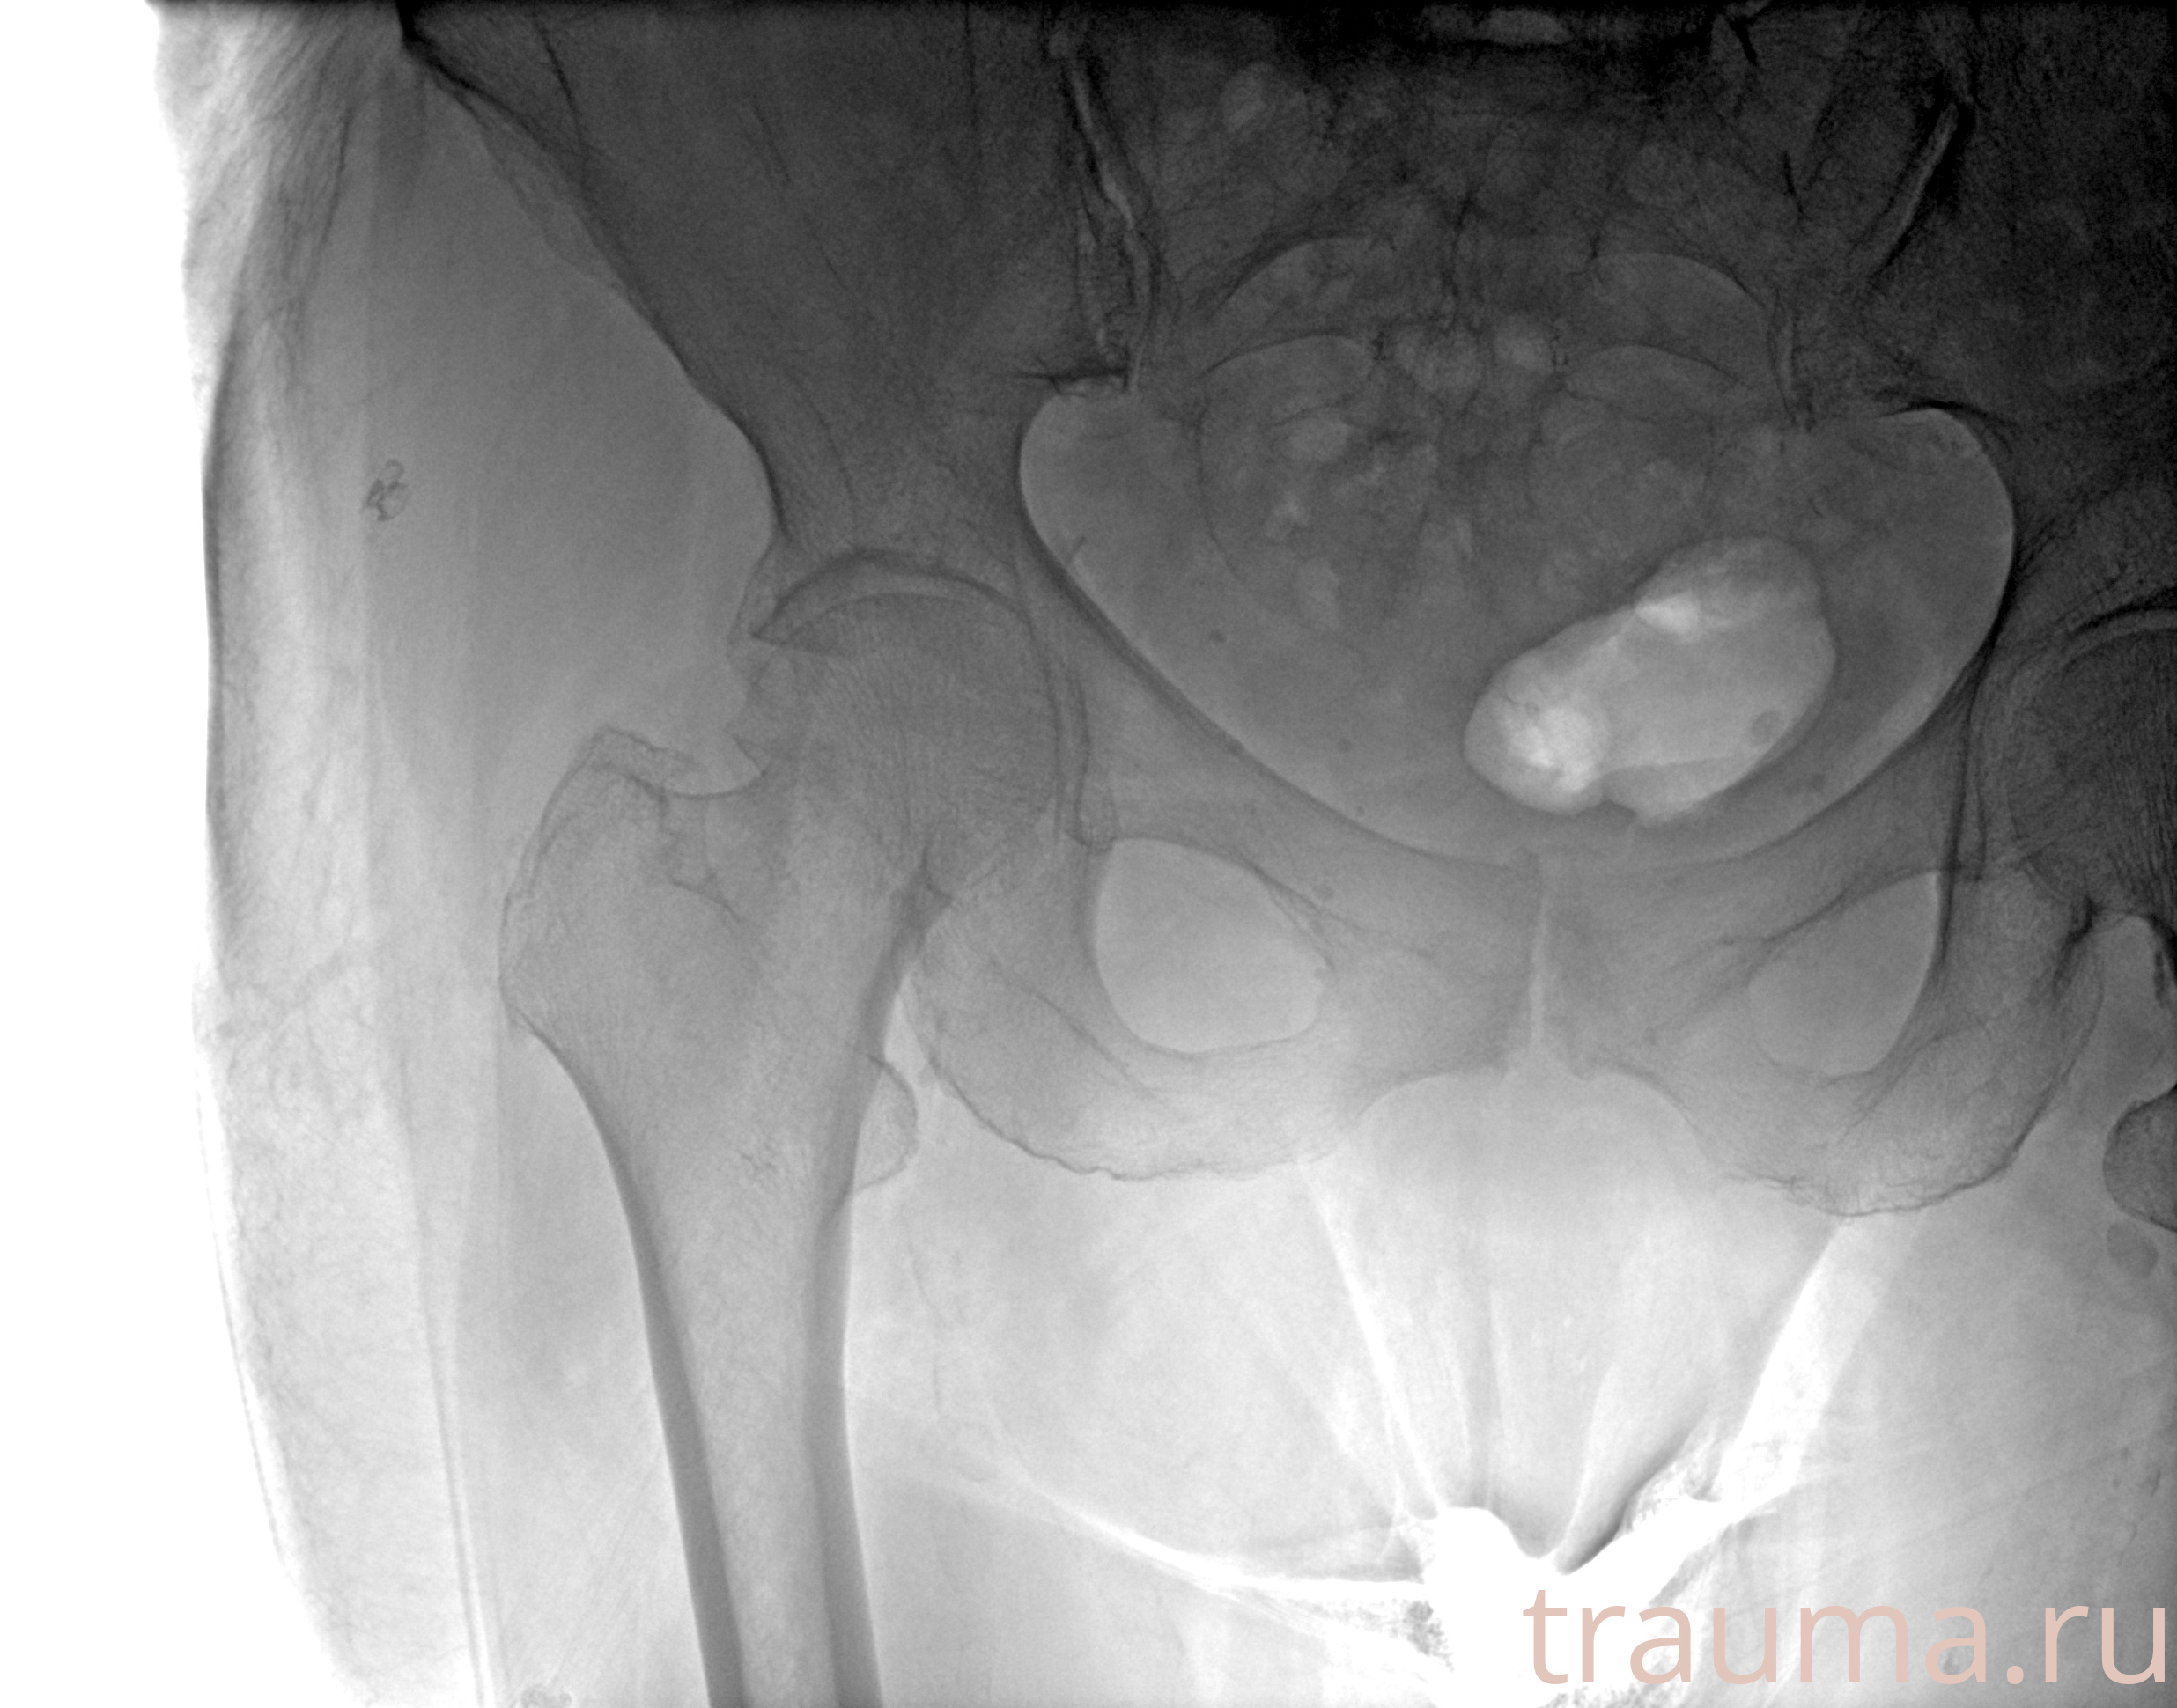

Рентгенограммы

Рентген на дому: по вашему адресу приезжает врач-рентгенолог, травматолог-ортопед с мобильным рентгеновским аппаратом, проводит диагностику травмы или заболевания, делает необходимые рентгенограммы, дает рекомендации по дальнейшему лечению. Получить качественные снимки в домашних условиях возможно благодаря уникальной методике, разработанной МосРентген Центром для института  Склифосовского